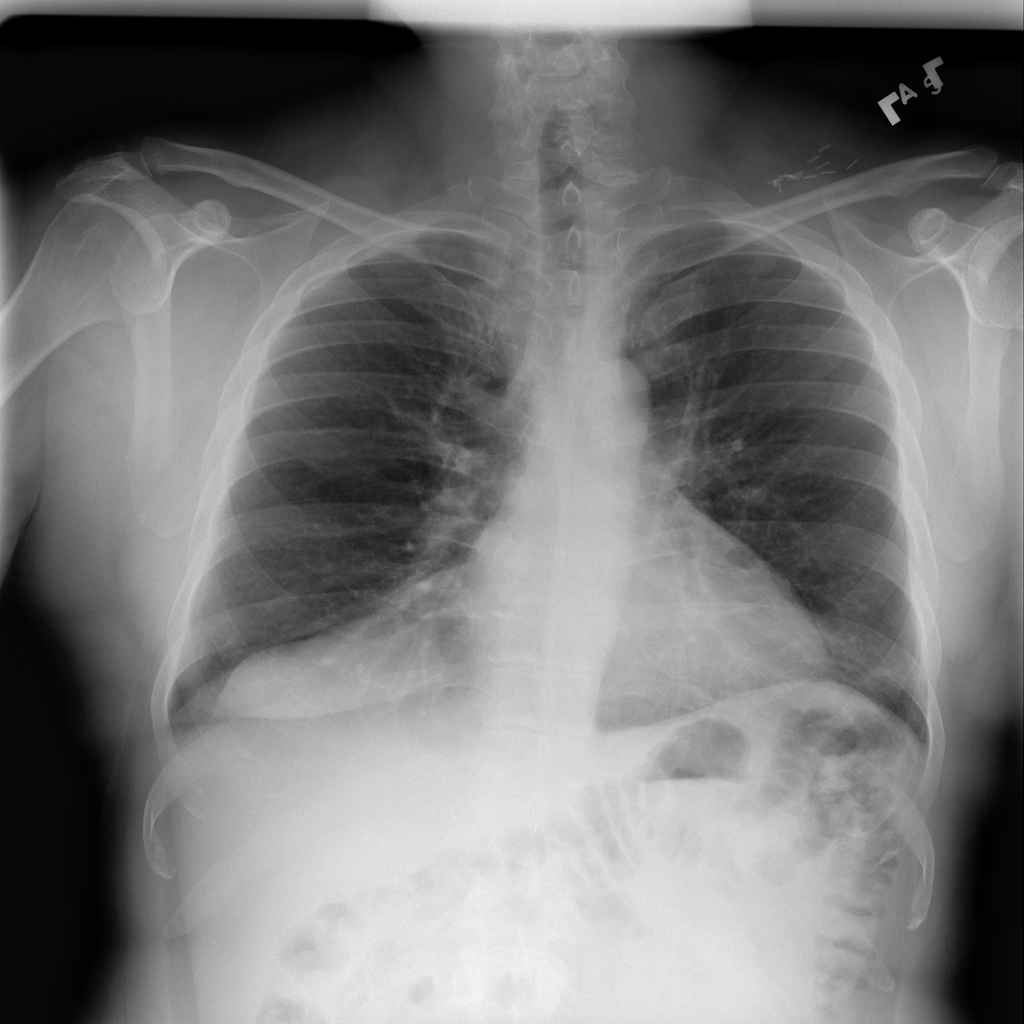

PAT-B3C3 · IMG-001Pneumonia

PAT-B3C3 · IMG-001

PA